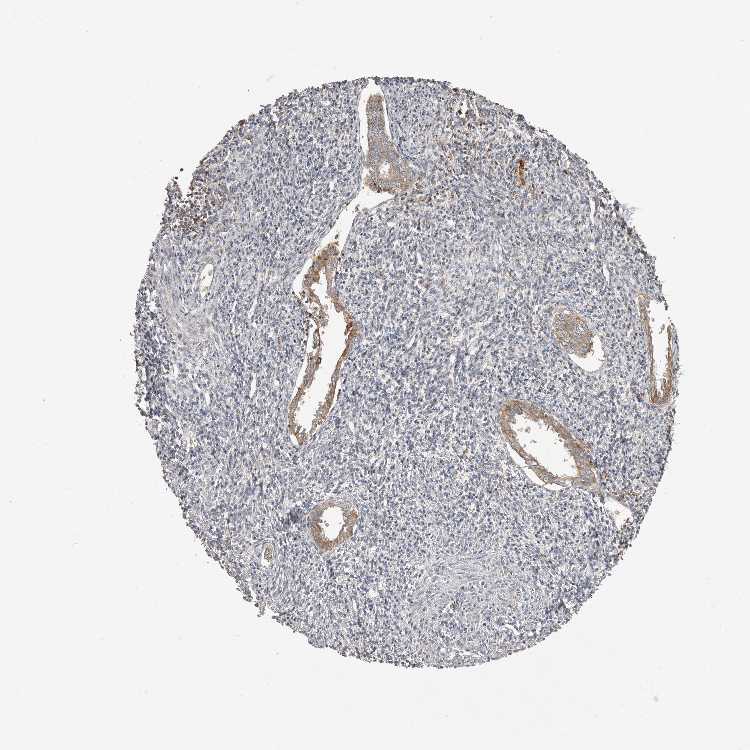

ENDOMETRIUM 1 - Antibody stainingi

Antibody staining in the annotated cell types in the current human tissue is reported as not detected, low, medium, or high, based on conventional immunohistochemistry profiling in selected tissues. This score is based on the combination of the staining intensity and fraction of stained cells. Each image is clickable and will lead to virtual microscopy that enables deeper exploration of all samples and also displays staining intensity scores, fraction scores and subcellular localization as well as patient and tissue information for each sample.

Antibody HPA026980

Cells in endometrial stroma Not detected

Glandular cells High